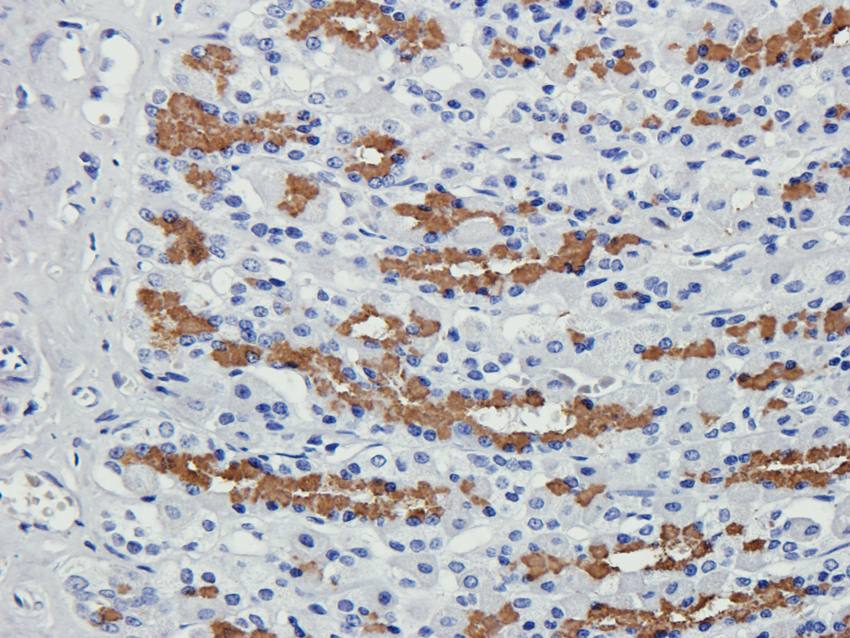

10 μg, 100 μg - Cubilin antibody [orb4997]Featured

ICC, IF, IHC-P, WB

Human, Mouse, Porcine, Rat

Rabbit

Polyclonal

Unconjugated

100 μg - PGP9.5 antibody [orb6713]Featured